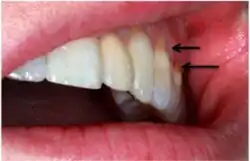

Non-carious cervical lesions (NCCLs) are a group of lesions that are characterised by a loss of hard dental tissue at the cementoenamel junction (CEJ) region at the neck of the tooth, without the action of microorganisms or inflammatory processes.[1] These lesions vary in shape from regular depressions that look like a dome or a cup, to deep wedge-shaped defects with the apex pointing inwards.[1] NCCLs can occur either above or below the level of the gum, at any of the surfaces of the teeth.

A systematic review by Teixeira et al. reported that most diagnoses of NCCL are derived from a combination of visual and tactile clinical examinations[11] under adequate illumination. This is depicted as a clinical loss of mineralized dental tissue at the cementoenamel junction (CEJ) in the buccal or lingual dental surfaces. There is also a consensus that visual dentine exposure is a reliable indicator of loss of tooth tissue.[14]